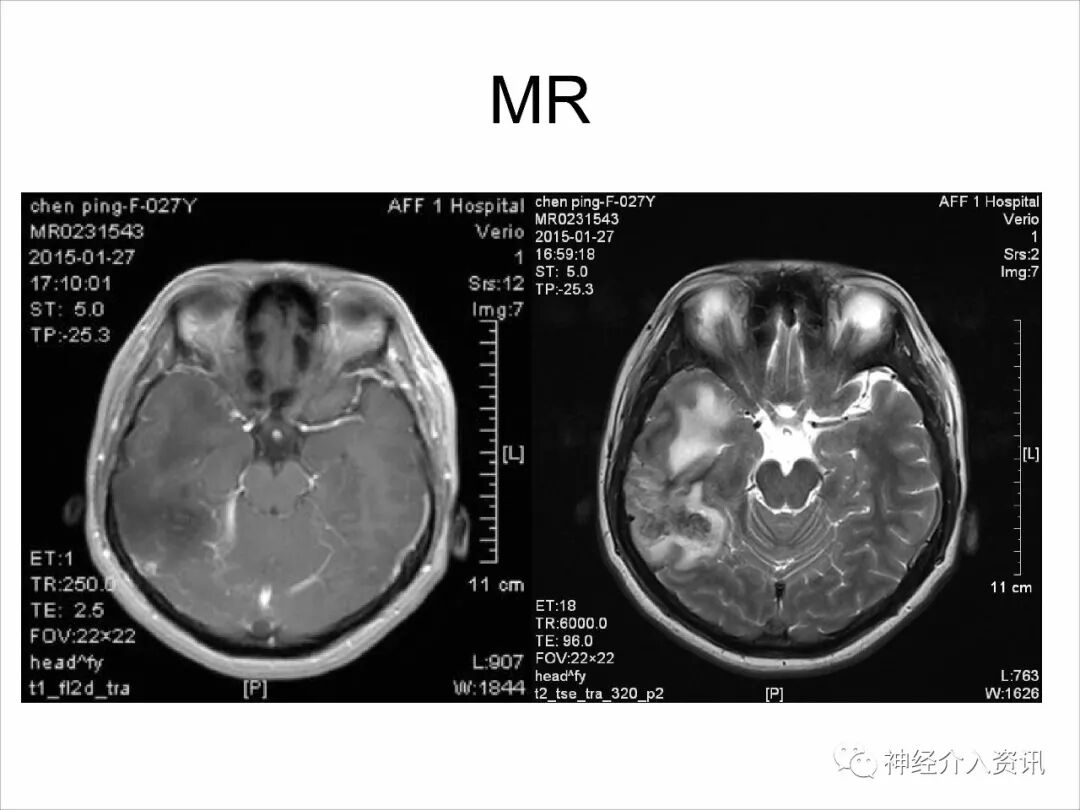

今天为大家分享的是由福建医科大学附属第一医院戴琳孙教授在第十二届华东地区脑血管病血管内治疗大会上带来的“脑静脉窦血栓的血管内治疗”精彩讲课视频和PPT,欢迎观看!(内容未经讲者审核,不当之处请与我们联系)